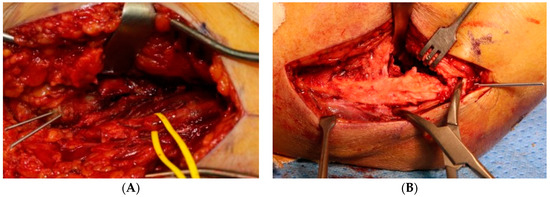

All surgeries were performed in the supine position under general anesthesia using a tourniquet. Each approach was performed using standard methods [14,15,16,17]. In the posterior approach, the ulnar nerve was first identified and protected. In cases of severe intra-articular fracture fragmentation, olecranon chevron osteotomy is performed. Subsequently, depending on the surgeon’s preference, either orthogonal, parallel, or single 3.5 LCP distal humerus plate (DuPey Synthes, West Chester, PA, USA) fixation or TBW fixation was performed (Figure 1A–D). Anatomical reduction was implemented as much as possible to achieve absolute stability, and at least three cortical or locking screws were inserted proximally and distally.

Figure 1.

Fixation method (A) orthogonal plate, (B) parallel plate, (C) single plate, (D) tension band wiring.